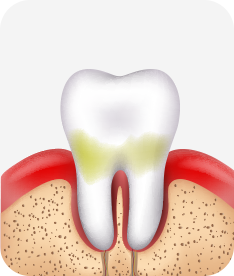

법랑질 충치

치아는 자각증상이 없을 수도 있음.

이 시기의 충치는 반드시 제거해야할 필요는 없으며 정기적 관찰과 예방 및 비침습적인 치료를 통해 충치의 진행단계를 늦추거나 멈출 수 있음.

치료방법 예방치료인 실란트, 불소도포, 정기검진

상아질 충치

찬 공기나 물에 닿을 때나 양치시

자각증상이 있을 수 있으며, 치아가 음푹 패이거나 삭을 수 있음. 치료하지 않으면 충치의 진행이 빨라질 수 있음.

치료방법 레진 충전, 인레이 등 수복치료

치수염 충치

밤에 잠을 이루지 못할 정도로 아프거나 찬 것과 뜨거운 것에 통증이 있을 수 있으며, 도중에 나은 것처럼 증상이 없어지는 경우도 있음. 치아의 경조직 뿐 아니라 치수까지 염증이 생긴 상태.

치료방법 신경치료, 크라운 등 보철치료